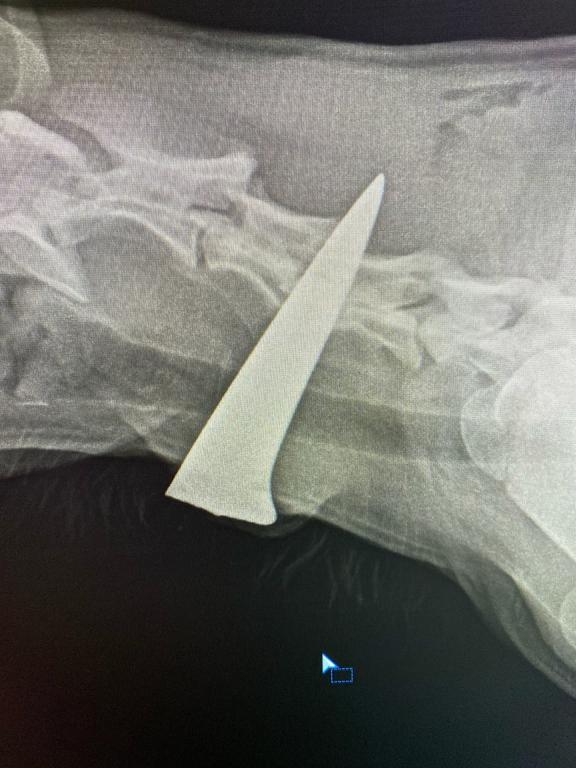

Пациентом Медведевской ветеринарной станции стала собака с ножевым ранением. Привезли её неравнодушные жители Килемарского района.

На шее животного торчало лезвие ножа, с которым, по оценке специалистов, собака проходила не меньше семи дней. Чудом не задеты жизненно важные артерии и вены, нет повреждений трахеи и пищевода. Добрые люди подкармливали и наблюдали за ней, они же привезли её на ветстанцию.

Как рассказали ветеринары, в настоящее время четвероногому питомцу сделали операцию, извлекли лезвие, провели хирургическую обработку ран и назначили курс антибактериальных препаратов.

Фото: Медведевская ветеринарная станция